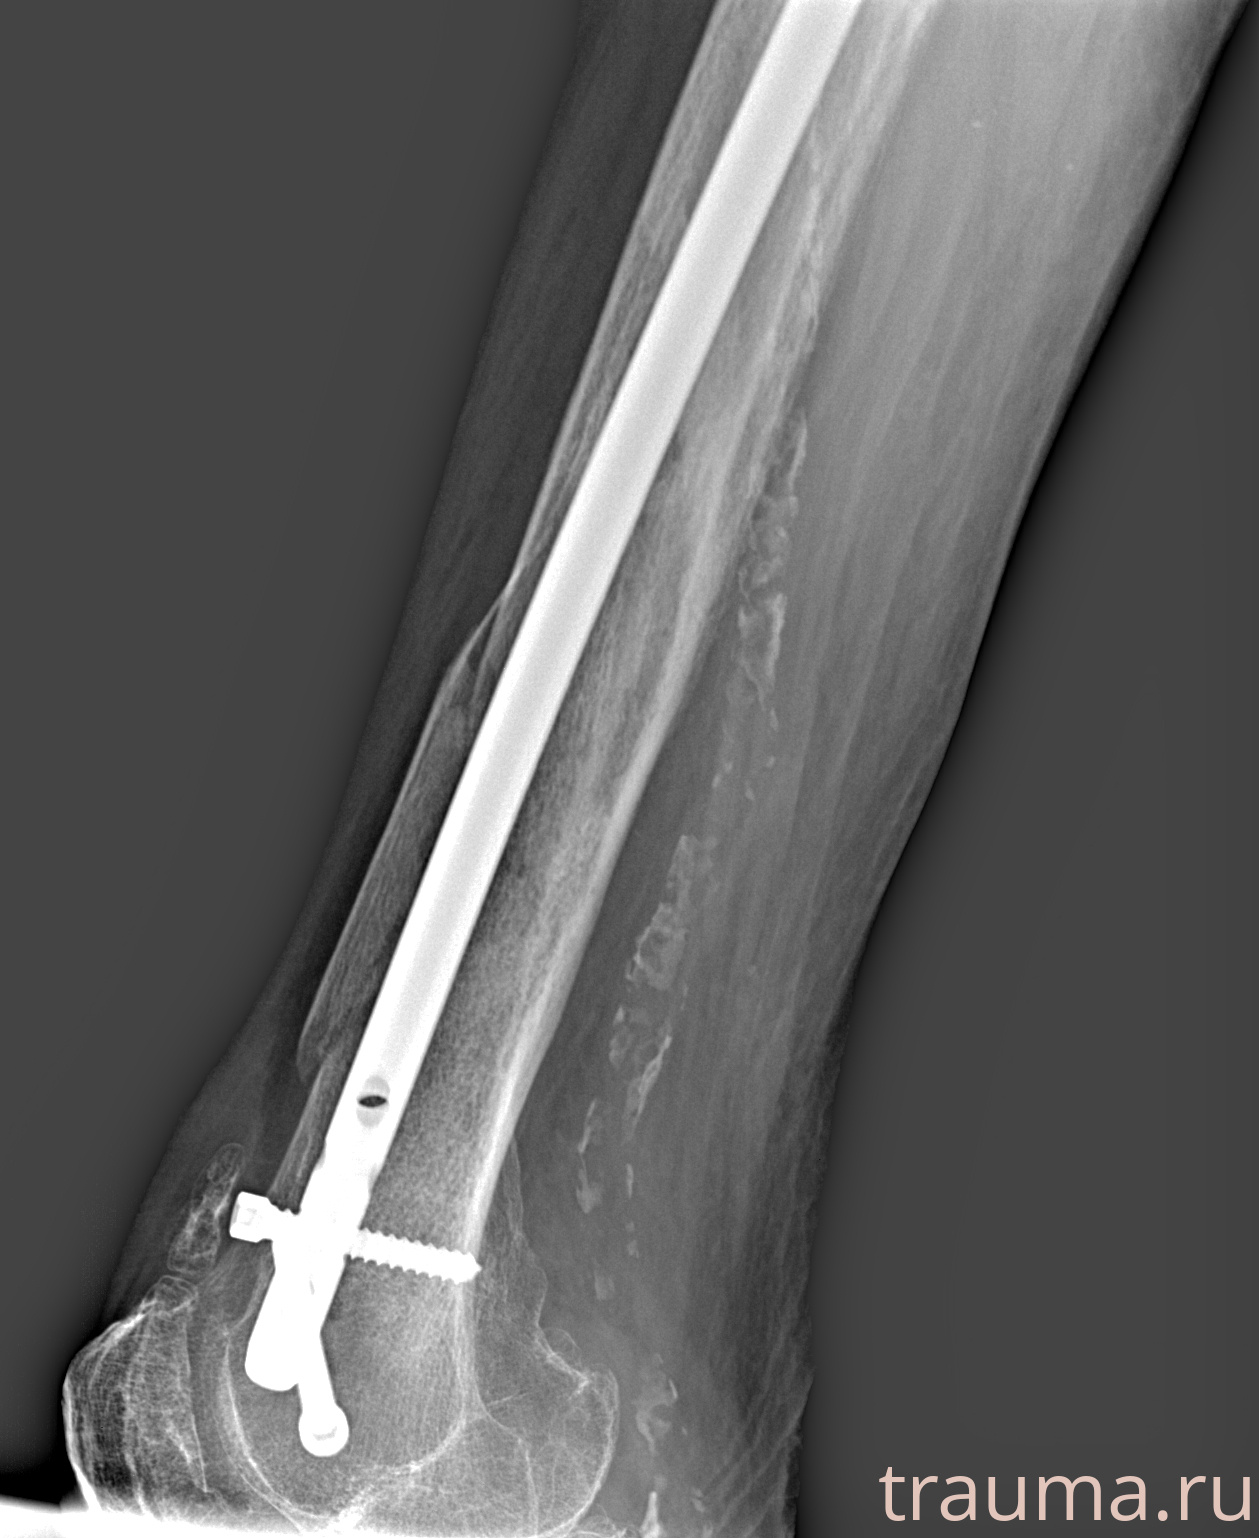

Рентгенограммы

Рентген на дому: по вашему адресу приезжает врач-рентгенолог, травматолог-ортопед с мобильным рентгеновским аппаратом, проводит диагностику травмы или заболевания, делает необходимые рентгенограммы, дает рекомендации по дальнейшему лечению. Получить качественные снимки в домашних условиях возможно благодаря уникальной методике, разработанной МосРентген Центром для института  Склифосовского